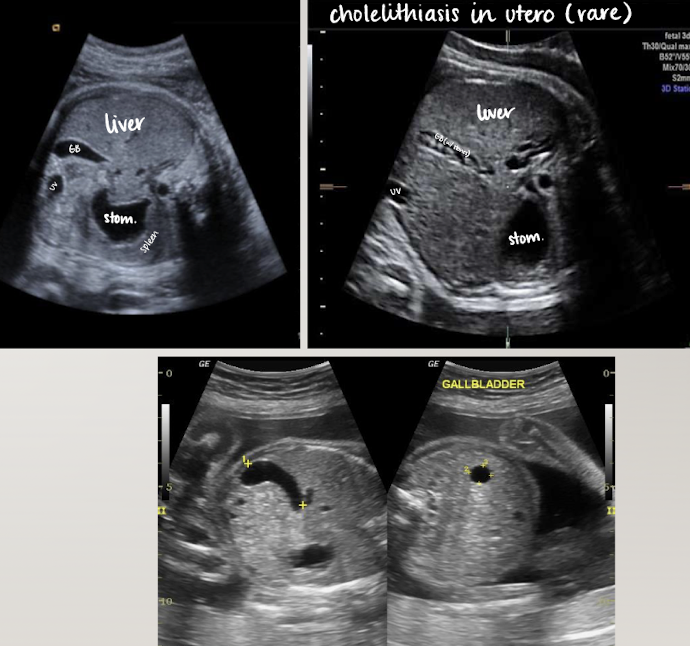

gallbladder

seen after 20 weeks

SONO: elongated anechoic structure in long-axis; circle in short-axis

in right abdomen near liver

more oval than intrahepatic umbilical vein

document presence